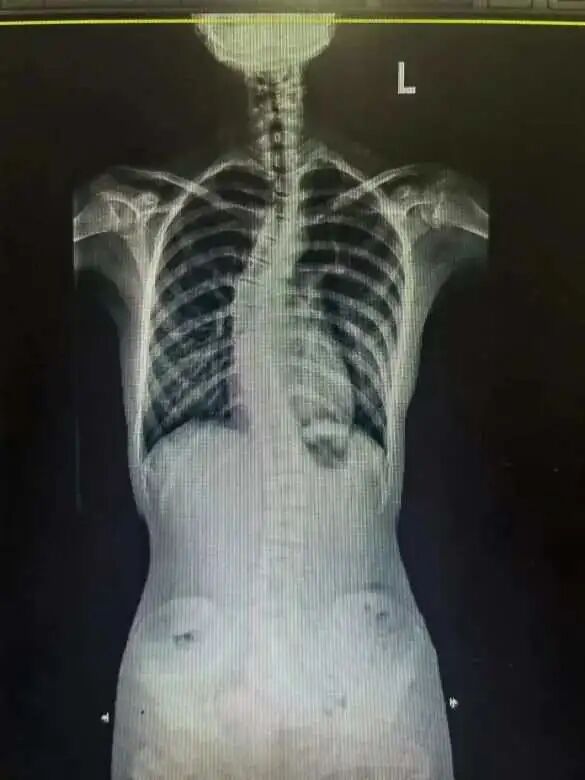

接诊专家叶文松主任医师告诉她,孩子这种情况确实考虑特发性脊柱侧弯。后来的检查结果显示,跳跳的侧弯曲角度已经达到45度。医生表示,跳跳的这种情况,需要手术矫治,12节胸椎骨要动10节,在手术中还要给跳跳打入18颗螺钉。

跳跳手术前

跳跳手术后

一家人最终下决心给跳跳做手术。手术非常顺利,跳跳不仅解决了脊柱侧弯问题,还长高了3厘米。现在,手术已经过去半年,跳跳早已能跑能跳,人也笔挺了。

叶文松主任医师表示,从跳跳的恢复情况看,这是一个非常成功的手术案例,但也不无遗憾,如果家长早点带孩子来评估,就可以用支具固定进行矫正。“但从我们临床经验来讲,这个孩子来看得还不算晚的,不少来的时候侧弯曲角度已经超过50度,有的甚至达到70度,胸椎、腰椎都要手术。有个女孩侧弯曲度高达90度,不仅所有胸椎骨都要动,几乎所有腰椎骨也要动,创伤就大得多,术后对未来生活的影响也会大得多。”